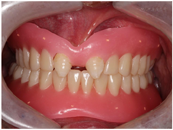

口外检查:颜面部表情自然,意识清楚,无关节弹响压痛,无张口受限,开口4.5cm,最大辅助开口5cm。面部左右不对称,颏点右偏,开口右侧偏斜。口内检查:上颌余留#17,11,21,27,畸形牙;下颌全口牙缺失,牙槽嵴萎缩,角化龈萎缩。唇部肌肉对抗牵拉力量较强,前庭沟浅(图4,图5,图6)。

术前检查发现患者20多年来的不良咬合,唇部张力过大,拟采用全口活动义齿恢复咬合高度,进行咬合重建。制取印模,并制作诊断蜡型,患者对蜡型的美学效果满意后试戴全口义齿,检查全口义齿就位、咬合高度、边缘、颜色等,均能达到治疗需求。对患者戴用修复体时要注意的问题及口腔卫生维护进行强调。咬合重建3个月后检查,患者不伴有咀嚼肌压痛、关节区压痛及弹响音等症状,无不适感(图10)。